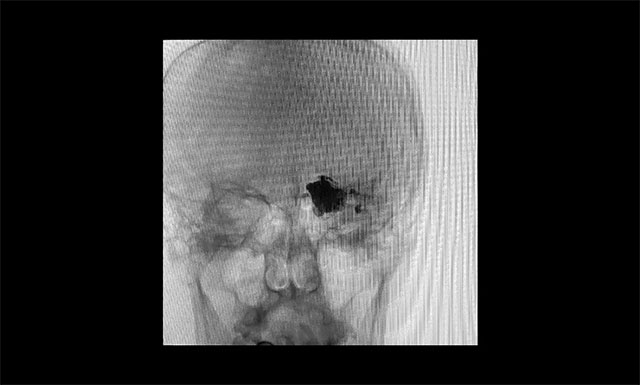

▲ 微导管造影确认后,注入 Onyx 18胶7.5ml

▲术毕铸型